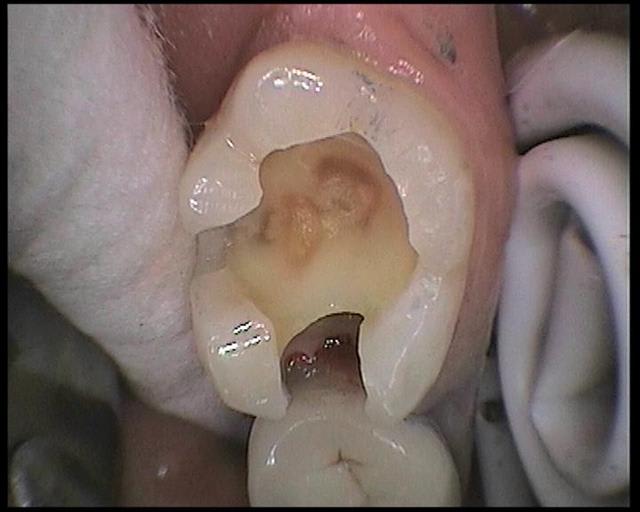

voici les images prises avec la sopro 595

Images en vrac de sopro 595